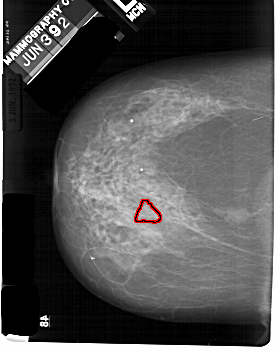

A_1824_1.LEFT_CC

FILE: A_1824_1.LEFT_CC.OVERLAY

TOTAL_ABNORMALITIES 1

ABNORMALITY 1

LESION_TYPE CALCIFICATION TYPE PLEOMORPHIC DISTRIBUTION SEGMENTAL

ASSESSMENT 4

SUBTLETY 3

PATHOLOGY MALIGNANT

TOTAL_OUTLINES 1

BOUNDARY